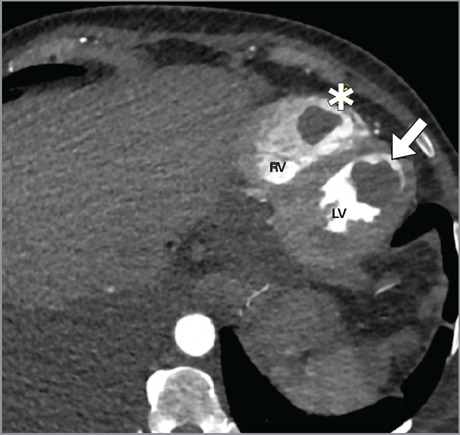

左、右心室同时形成血栓极为罕见,其临床特点及预后尚不清楚。因此,治疗方法仍存在争议。本病例强调了内窥镜取栓术作为治疗心功能受限患者巨大漂浮双室血栓的可行选择的潜力。经主动脉瓣和三尖瓣入路可以有效、完全地清除血栓,从而防止进一步的栓塞并发症。

The simultaneous formation of thrombi in the left and right ventricles is extremely rare, and this condition's clinical characteristics and prognosis remain unknown. Therefore, treatment methods are still controversial. This case highlights the potential for endoscopic thrombectomy as a viable option for the treatment of giant floating biventricular thrombi in a patient with restricted cardiac function. This approach via the aortic and tricuspid heart valves allowed for effective and complete removal of the thrombi, thereby preventing further embolic complications.